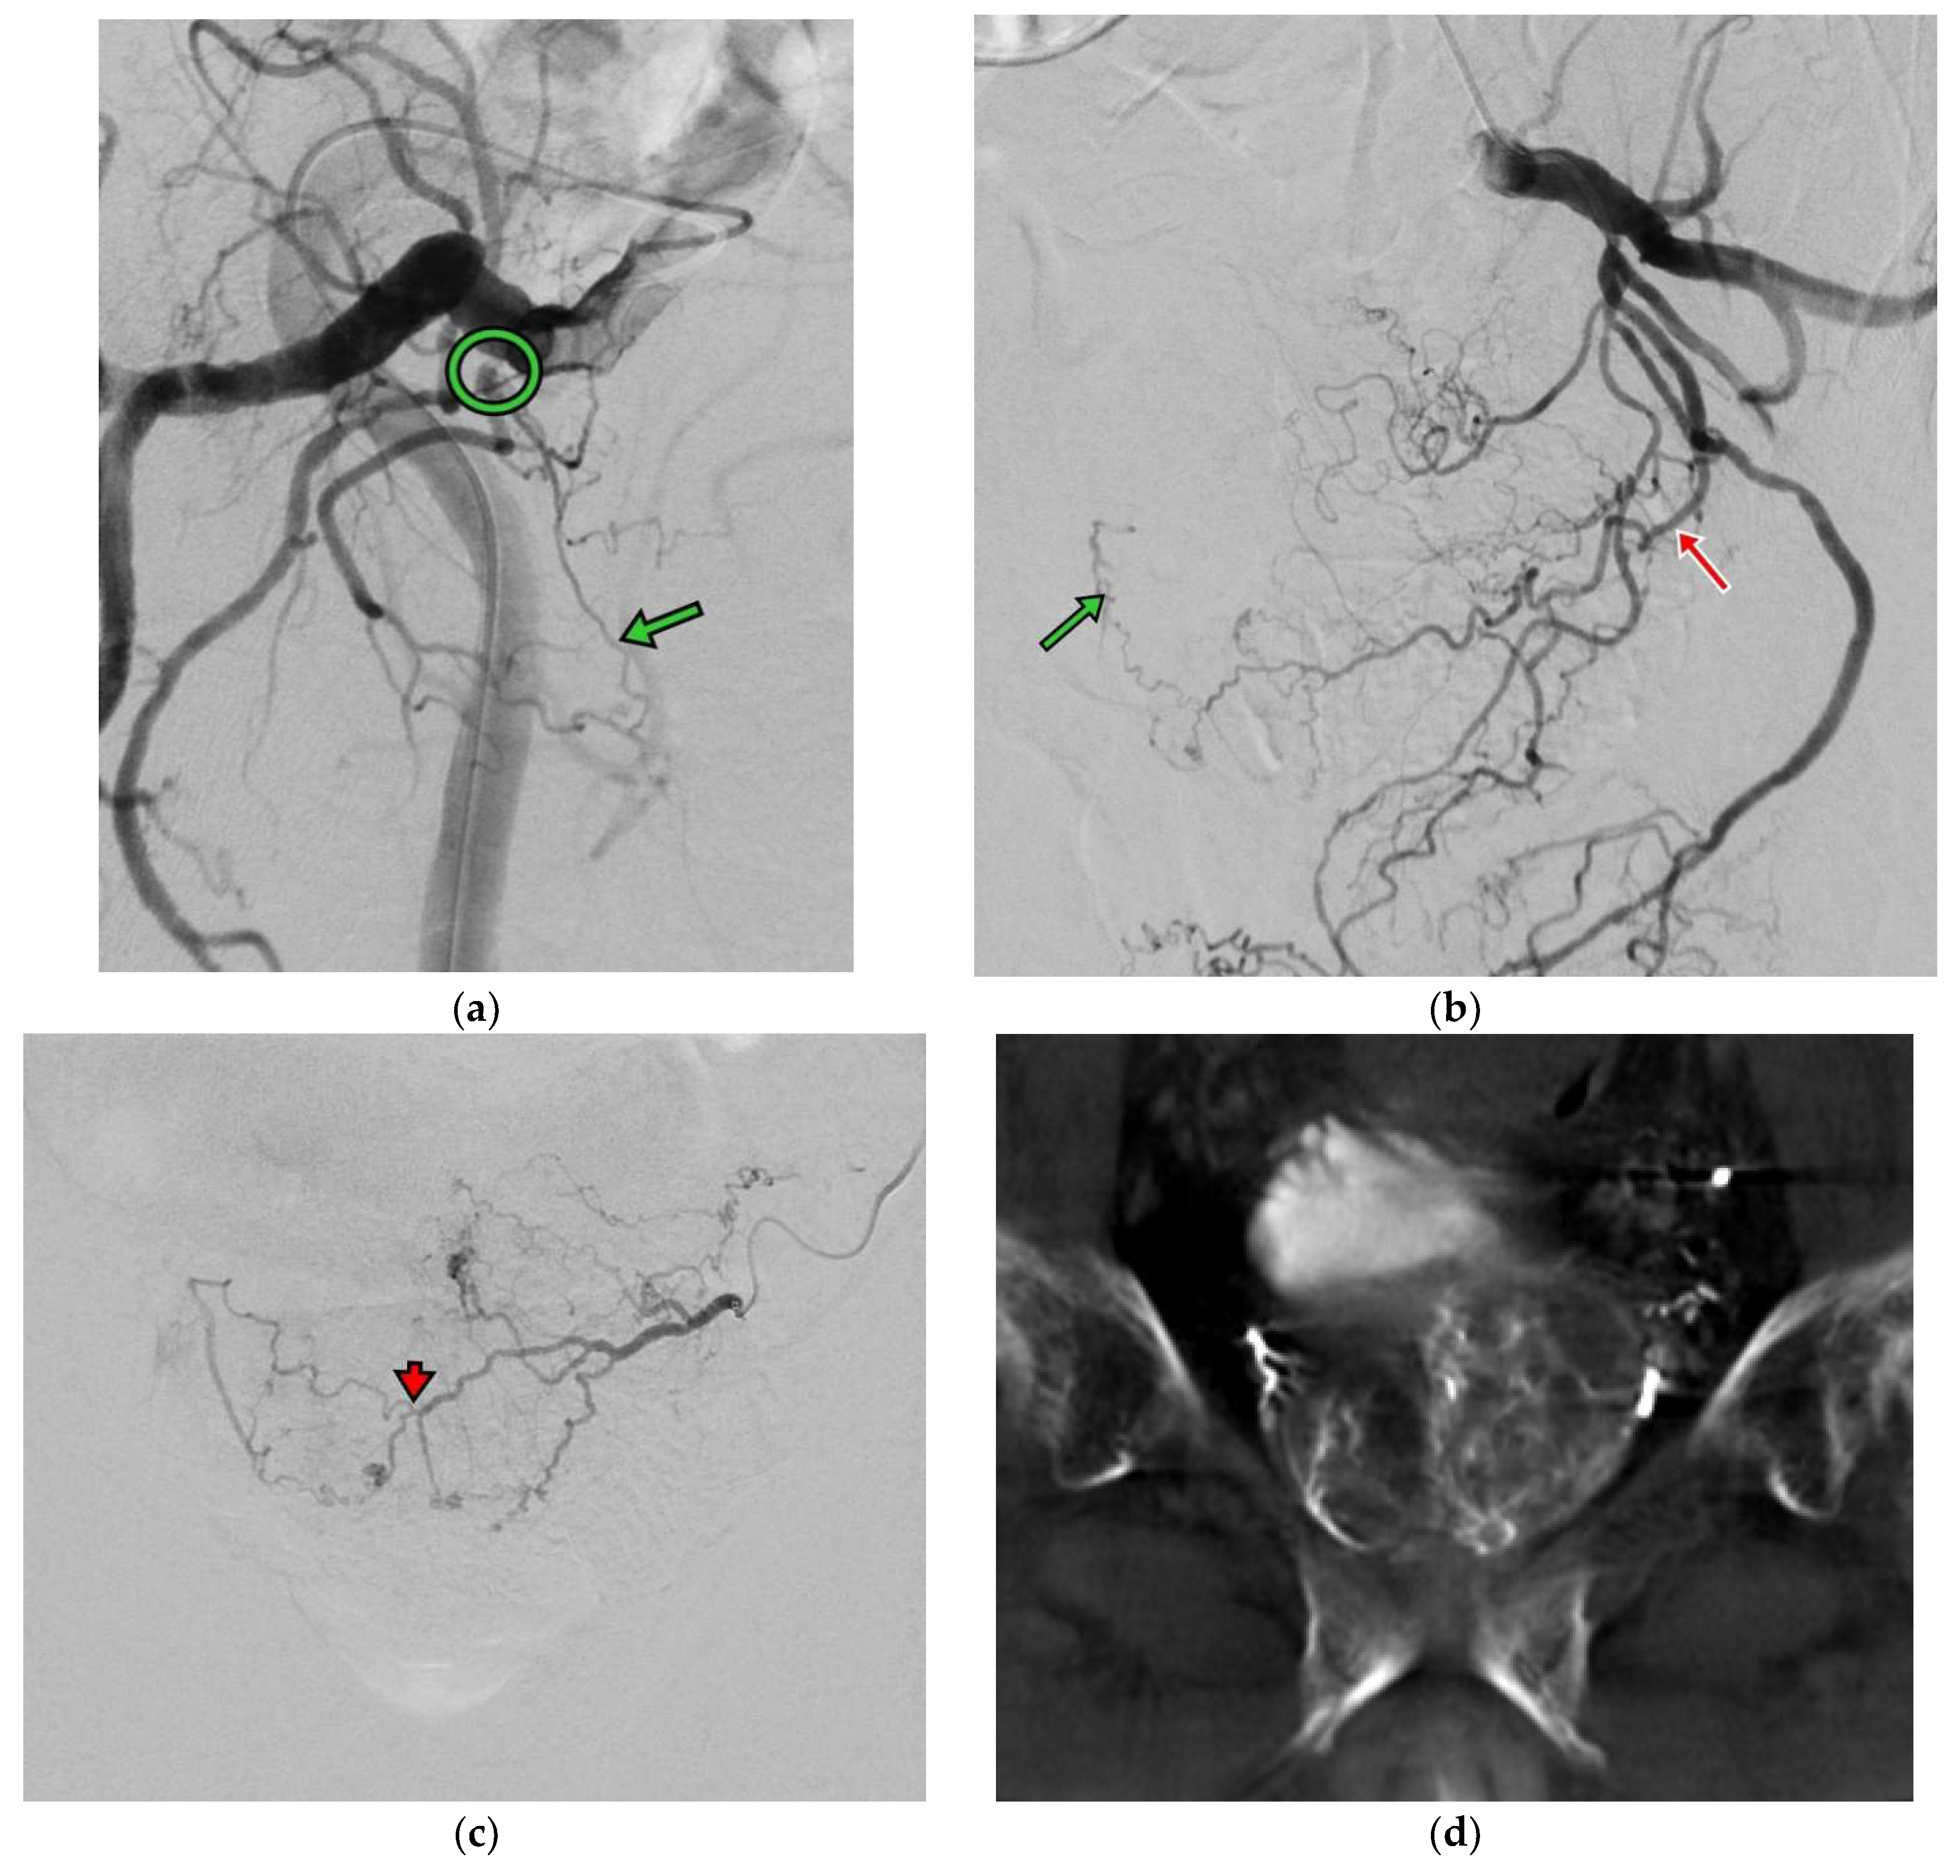

The PAE procedure was performed via left distal transradial access (dTRA). After local anesthesia (LA), 3000 IU heparin was injected via sheath. A 125 cm catheter (Ultimate, Merit Medical Inc., South Jordan, UT, USA) was introduced via distal radial artery straight down to the common iliac artery and was navigated to the right internal iliac artery. The procedure was complicated using severe stenosis in the anterior division of the right internal iliac artery, and a microcatheter advancement toward the right prostate artery was not feasible. Right femoral access was attempted but again failed due to stenosis (Figure 2a). Left prostate artery showed both sides’ prostate perfusion and was inaccessible to a 2.4 F microcatheter (150 cm Maestro, Merit Medical Inc.) through intraprostatic anastomosis (Figure 2b,c). A pre-filled syringe of 300–500 um Tri-acryl gelatin microsphere (Embosphere, Merit Medical Inc.) was mixed with 10 mL iodinated contrast agent, and 1 mL of the microsphere was injected slowly until the antegrade flow stopped. Bilateral PAE was performed by injection with microsphere from the left prostate artery. Procedural time was 220 min. Hemostasis by compression was performed for 2 h and bedrest was performed for 4 h. The patient was discharged on the next day without complications.

Figure 2.

(a) Right internal iliac angiography (oblique view RAO 30 degrees) shows high grade stenosis (circle) at the branch of the right prostate artery (green arrow). (b) Left internal iliac angiography (oblique view LAO 30 degrees) shows the left prostate artery (red arrow) with contrast opacified at the right side of the prostate artery (green arrow). (c) Left prostate angiography (AP view) shows both sides’ prostate perfusion via intraprostatic anastomosis (arrowhead). (d) CBCT images show prostate perfusion at both sides on the left prostate angiography.

Aligned with previous investigations, our report also showed significant LUTS improvement from Severe at baseline to Moderate at 1 month and further down to Mild at 6 months. There was a 78.3% improvement relevant to 18 IPSS points at 1 year and good improvement at 2 years. PAE was demonstrated to be effective in reducing the prostate volume by 35% without any complications [7]. Although only the unilateral prostate artery was selected with the microcatheter, on both sides PAE was conducted for this case using a cone beam CT(CBCT) image to confirm. This is the first reported image to show a prostate perfusion on both sides of a unilateral prostate artery due to severe stenosis on the other side. Although unilateral PAE was performed for this case, which was shown to be one of the negative factors for clinical success, the clinical outcomes were found to be comparable to the existing reports [8]. In Bilhim et al., 2013, a bilateral PAE led to better clinical results, but 50% of patients who received unilateral PAE also showed a good clinical outcome, like in this case [8]. From our experience, unilateral PAE is considered a technical success, and an improvement of IPSS by 25% or more from baseline is determined as a clinical success. In this case, both technical and clinical successes were achieved, and PAE was shown to be safe and effective for elderly patients who are eager to treat the bothersome LUTS secondary to BPH. No symptom recurrence after PAE was identified.

Bilateral PAE might sometimes be difficult to achieve, especially in elderly patients with iliac/prostate artery stenosis and anatomical tortuosity [7]. Dr. Carnevale et al. also reported the technical aspects of PAE and the prognosis of unilateral PAE, where recurrence-free survival was found to be shorter than in bilateral PAE. The same finding was also reported in [8] Dr. Bilhim et al., in which the poor response rate was higher in unilateral PAE versus bilateral PAE (42% vs. 17.5%). In our clinical case reported here, there was a severe stenosis over the right prostate artery and the left prostate artery could support adequate blood flow towards the bilateral prostate glands via arterial anastomosis (Figure 2c,d). This finding suggested that we could evaluate the anatomy and the blood flow towards the prostate glands pre-operationally and start with the easy one first.